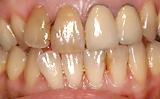

審美障害を主訴に来院されました。 | |||||||||||

| 30代女性の患者様です。インプラント治療、ブリーチング、ハイブリット冠で治療しました。噛み合わせも治療しています。見た目だけではダメです。 | ![]() |

【術前】 |

【術後】 |